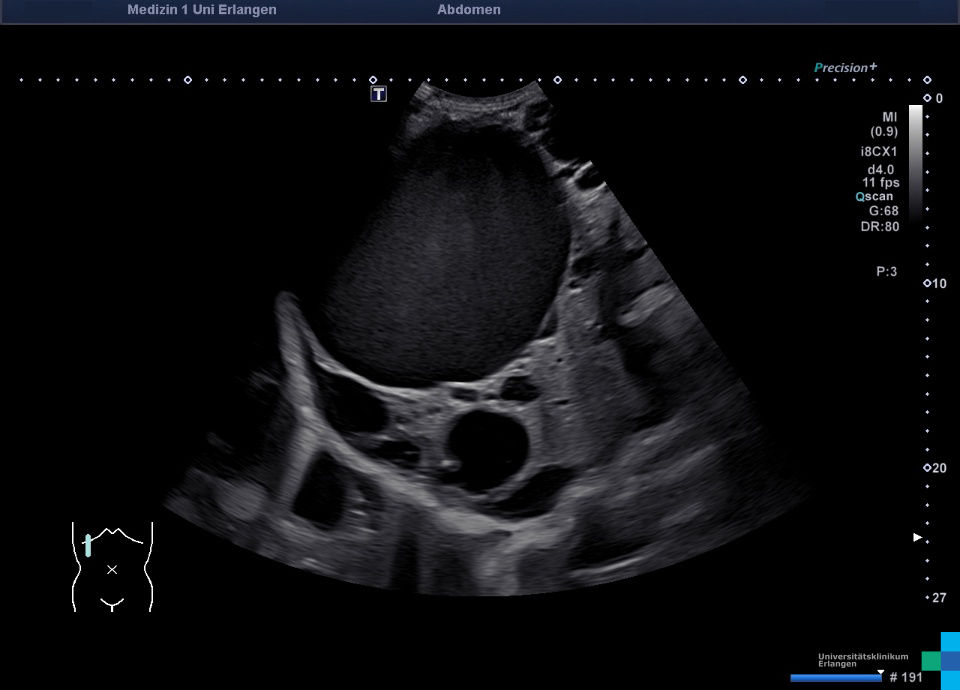

Echinococcal Cyst